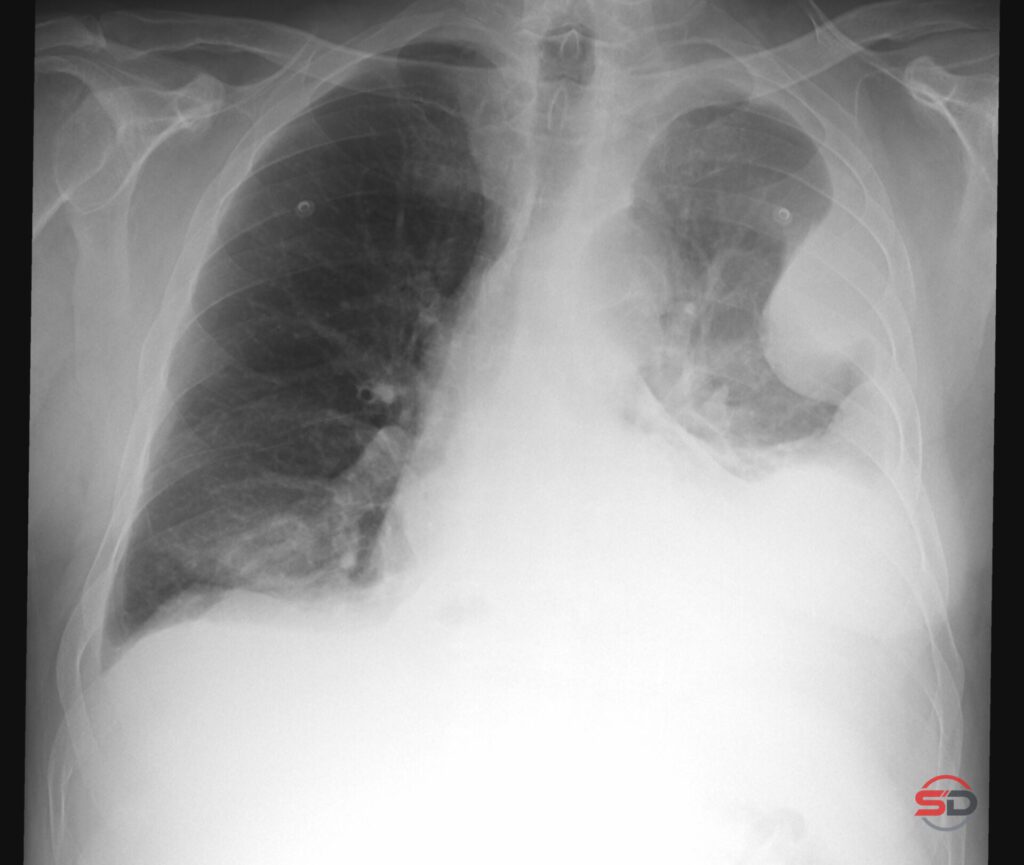

Pleuraerguss im Thoraxröntgen Der Pleuraerguss gehört zu den häufigsten Befunden in der konventionellen Thoraxdiagnostik. Im klinischen Alltag ist das Thoraxröntgen […]